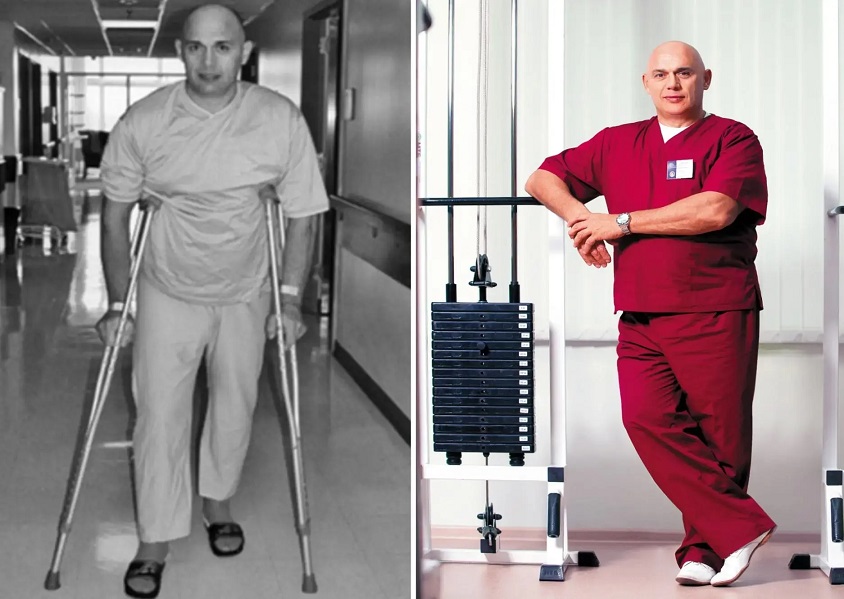

Доктор Сергей Михайлович Бубновский, д.м.н., международный эксперт высшей категории по ортопедии, мануальной терапии, лауреат премии за достижения в области суставной хирургии, автор уникальных методик восстановления суставов. Опыт работы в сфере — 30 лет.

— Движение — это жизнь. Знаете эту великую фразу Аристотеля? Теперь представьте, как меняется жизнь у людей, страдающих от болезней суставов?! Их сначала заставляют снимать симптомы обезболивающими. Потом это перестает помогать, и пациентов из коек пересаживают в инвалидные кресла, подсаживая на пожизненные препараты, как наркоманов! Прекрасные жизненные перемены!

В результате мы наблюдаем полное восстановление сустава, привычная подвижность возвращается через месяц-полтора.